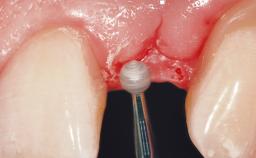

For soft tissue management, the initial healing caps are replaced with a longer type 8 weeks after implant placement in a second intervention before prosthodontic treatment is initiated.

The case concludes with the presentation of the final prostheses at the 3-year follow-up, demonstrating a stable and pleasing soft- and hard-tissue situation.